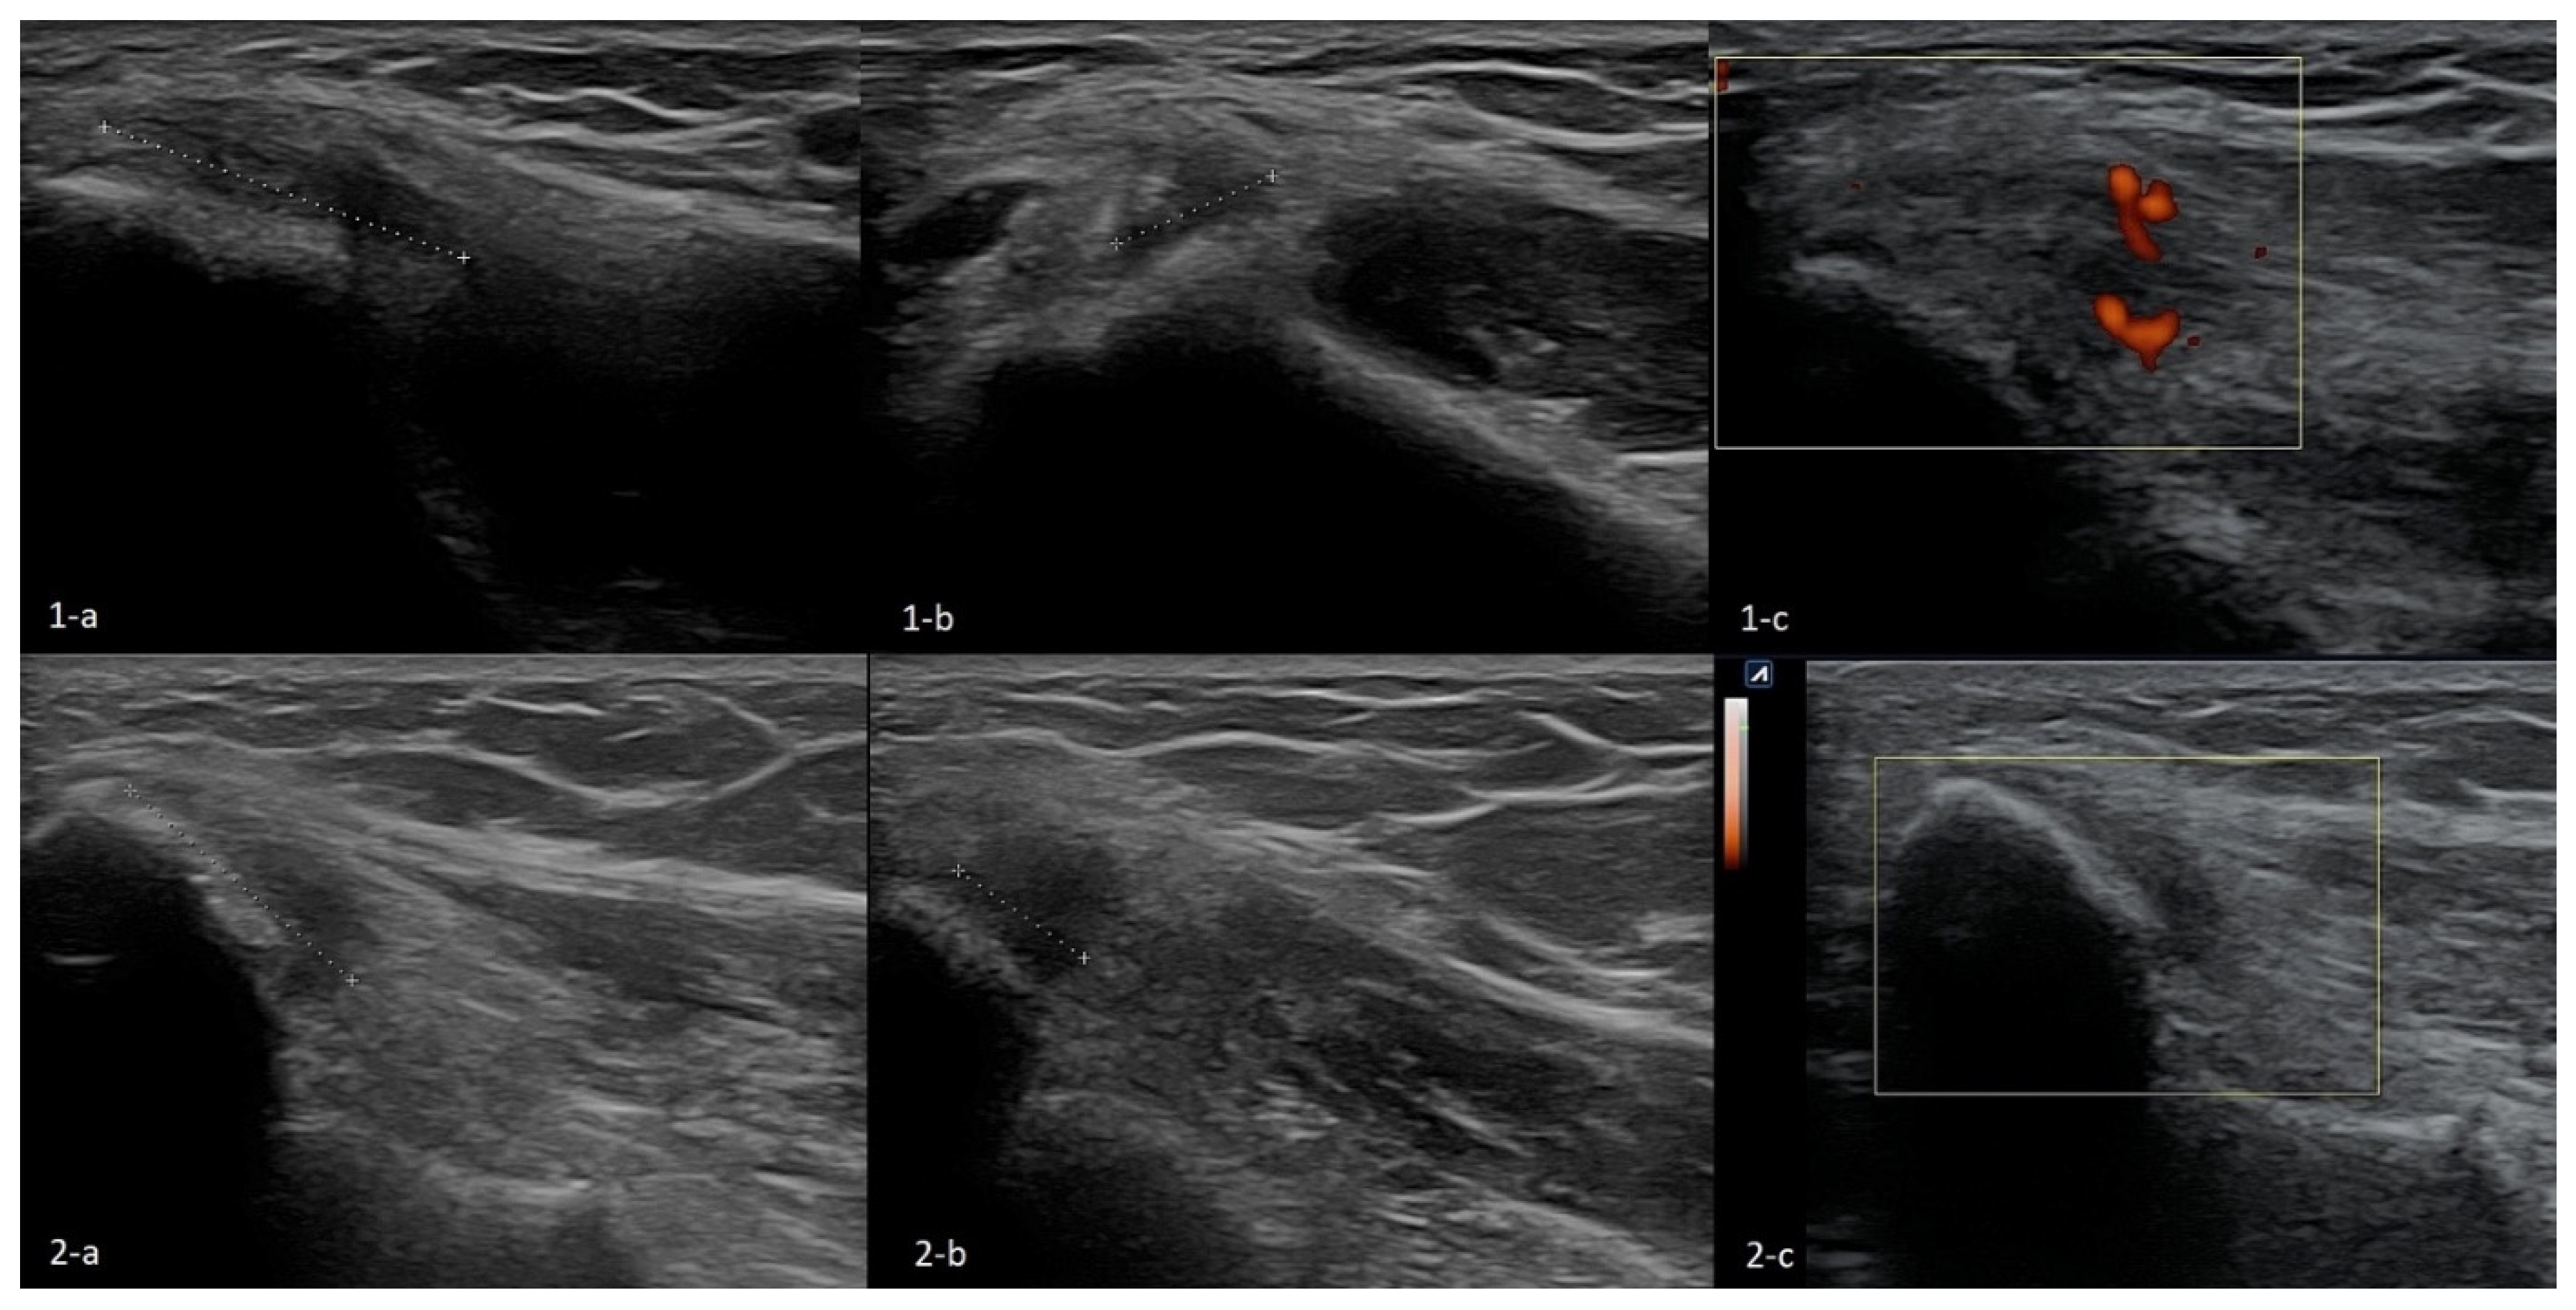

The Technique of Ultrasound Examination of the Medial Portion of the Elbow

4.2. Snapping Triceps with Ulnar Neuritis

4.3. Ulnar Nerve Compression Caused by Anconeus Epitrochlearis